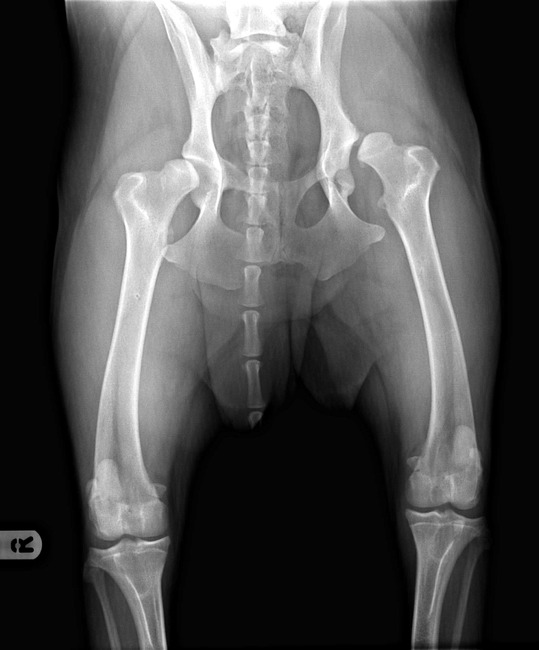

Inmiddels kon ik weer inloggen en heb een foto van de heupen van Puk op mijn profiel geplaatst. Weet niet hoe ik de foto bij mijn verhaal kan plaatsen.

Wat een rot situatie zeg. De heup foto's lieten me ook behoorlijk schrikken. Heb best weleens wat heupfoto's gezien die wat minder waren, maar geloof niet dat ik dit al eerder heb gezien

Oei, dat is schrikken die foto...

Zal hem er even bij zetten.

Oei als ik de foto zo zie heeft de hond idd erg veel pijn.

Bianca bedankt voor het plaatsen van de foto,

mijn eerste reactie op rontge foto.....sorry maar hij is foutief gemaakt....de hond ligt helemaal scheef....dat kun je zien aan ruggemerg...en bekken

en de achterpoten zijn verschillend van lengte

waardoor je een heel vertekend beeld ziet van de linkerkom

daarmee wil ik niet zeggen dat je hond geen hd heeft....maar misschien een andere gradatie

Ik ben erg geschrokken van die heupfoto!